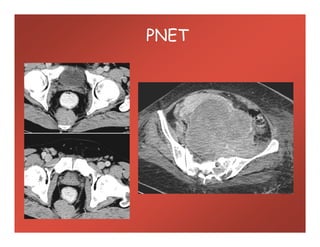

PNET